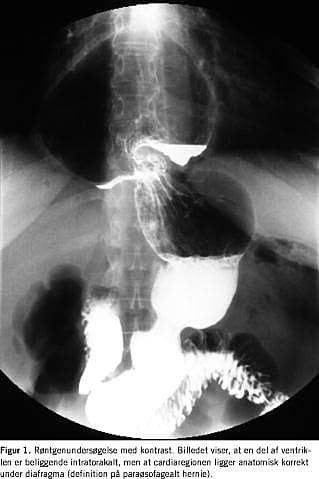

Ved klinisk mistanke bør der foretages røntgenundersøgelse af ventriklen med kontrast (Figur 1 ), hvorved diagnosen kan sikres. Gastroskopi kan benyttes, men de specielle anatomiske forhold gør en præcis beskrivelse vanskelig.

I perioden fra april 1999 til og med april 2002 behandlede vi 12 patienter, som var henvist med PEH og svære ledsagesymptomer . Disse patienter fik foretaget herniotomia paraoesophagealis laparoscopica. Der blev ikke foretaget åbne indgreb for samme tilstand i perioden. Retrospektivt registreredes demografiske oplysninger, præoperative symptomer, operative komplikationer samt postoperativ morbiditet og mortalitet. Præoperative undersøgelser inkluderede for alle gastroskopi og røntgenundersøgelse af den øvre mave-tarm-kanal med kontrast. Desuden fik ti patienter foretaget øsofagusmanometri, og fire patienter fik lavet 24-timers pH-undersøgelse vejledt af de kliniske forhold.